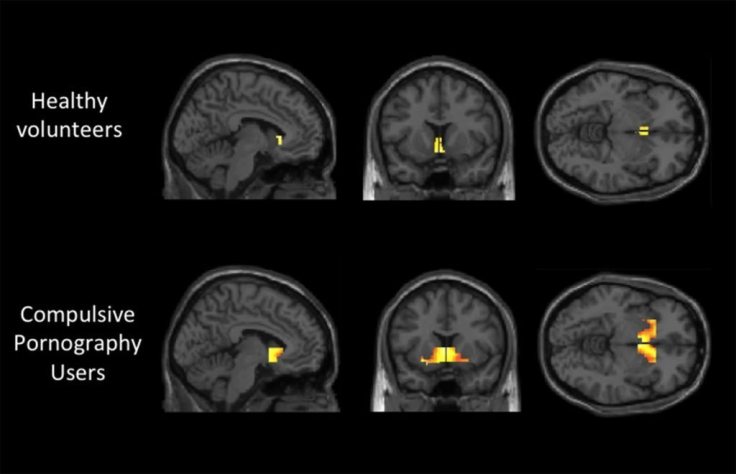

The study, titled Neural Correlates of Sexual Cue Reactivity in Individuals with and without Compulsive Sexual Behaviours, found strong evidence of sensitization in compulsive porn users. Sensitization is hyper-reactivity to cues that lead to craving and then to use. To put it simply, porn users become super sensitive to things that trigger them, which then give them the seemingly uncontrollable urge to look at porn. This process is considered to be the main change in the brain when it comes to defining addiction. As lead researcher Dr. Voon said about the study:

“There are clear differences in brain activity between patients who have compulsive sexual behaviour and healthy volunteers. These differences mirror those of drug addicts.”